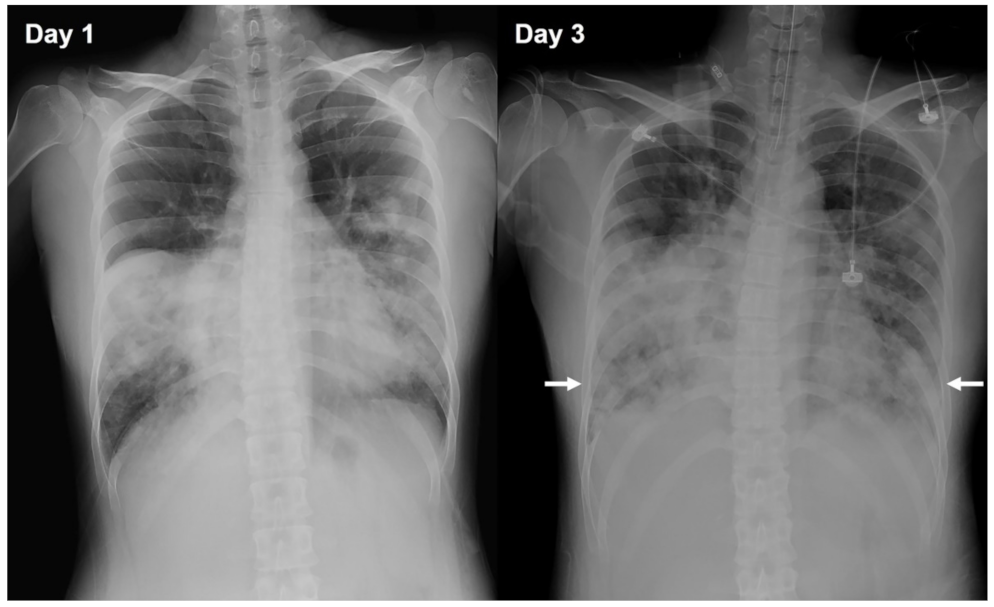

2. Case Presentation